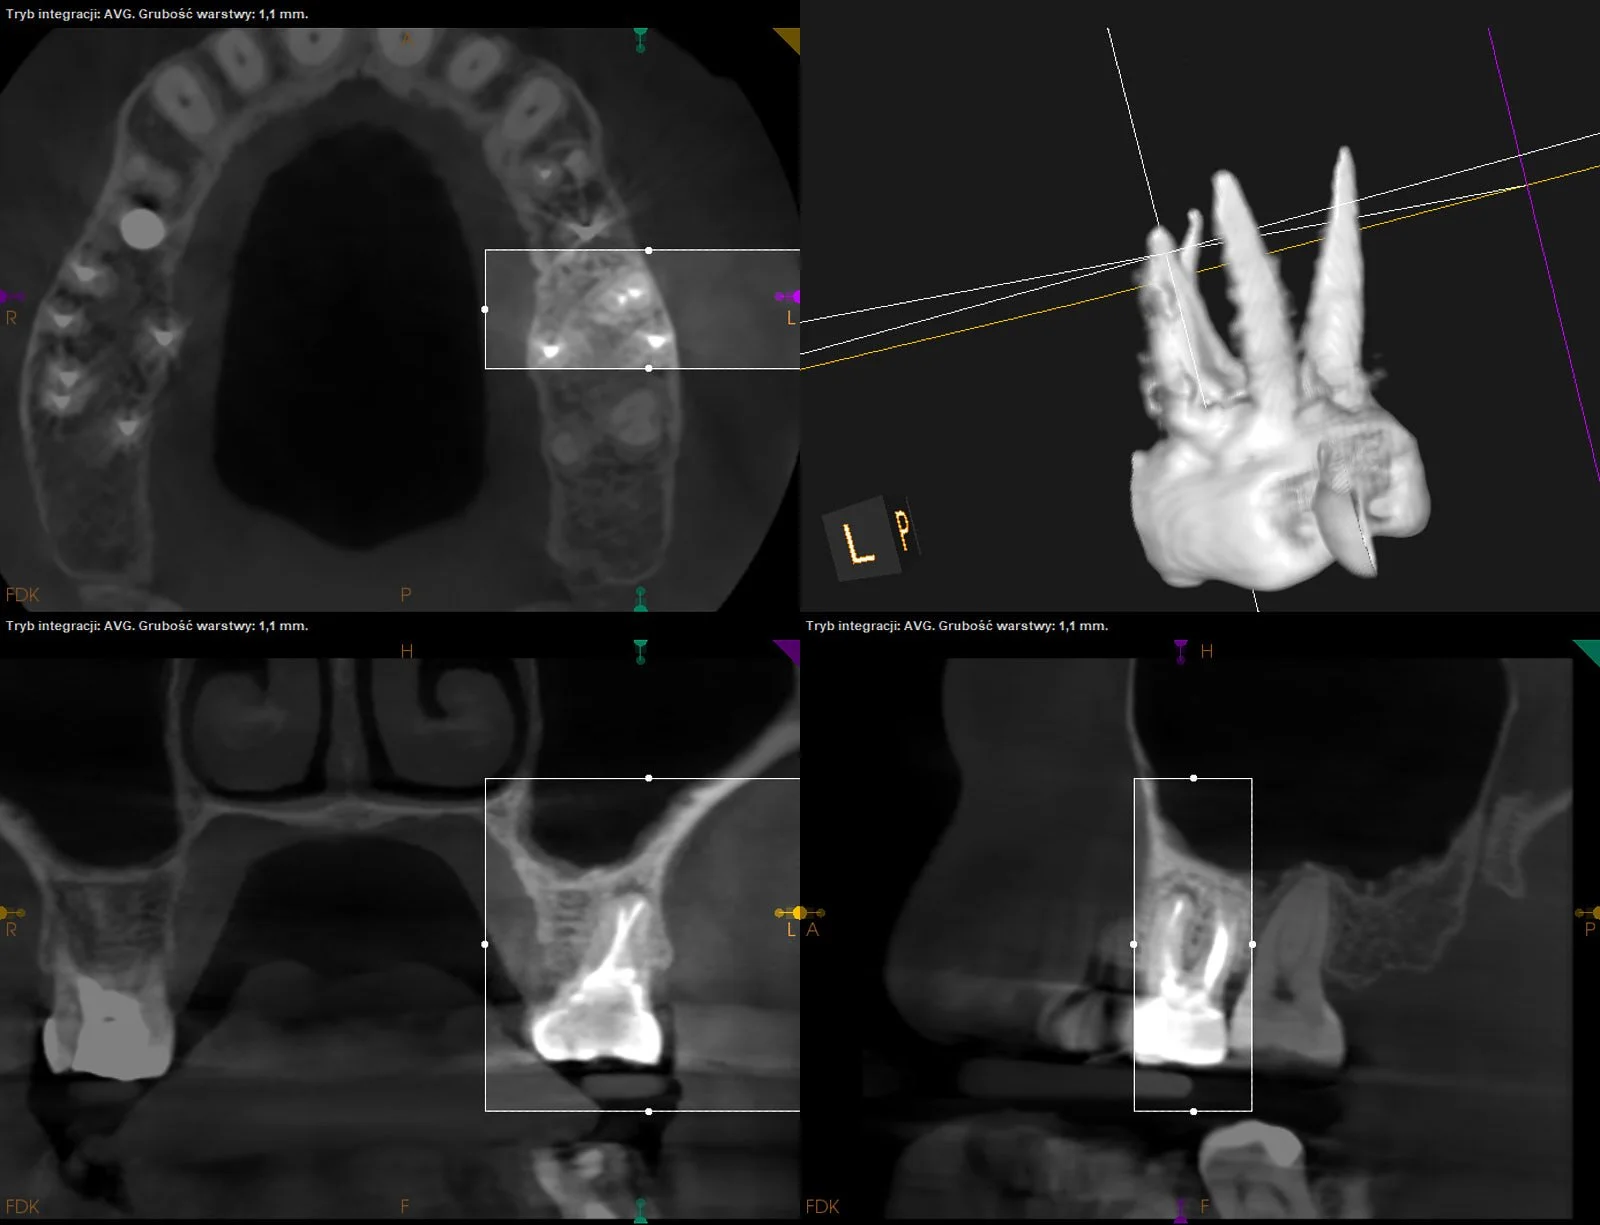

Gojenie okolicy okołowierzchołkowej przy korzeniu mezjalnym i dystalnym d.26 po ponownym leczeniu kanałowym (z uwagi na open apex w kanale dystalnym wykonano zamknięcie cementem MTA).